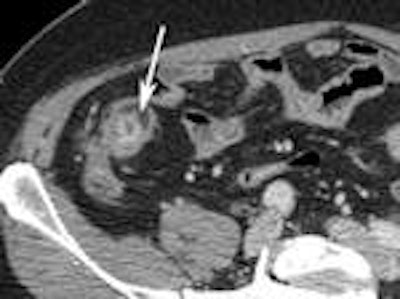

A 2007 study by University of Michigan gastroenterologist Dr. Peter D.R. Higgins showcases the diagnostic power of CT enterography (CTE) for evaluating small bowel Crohn's disease.

Higgins concluded that CTE offered complementary information about symptoms of obstruction in Crohn's disease (Inflammatory Bowel Diseases, March 2007; Vol. 14:3, pp. 262-268).

The following images from Higgins' study illustrate some of the clinically relevant findings about Crohn's disease that can be made with CTE.

Left: Bowel wall thickening. Right: Extraluminal fluid.